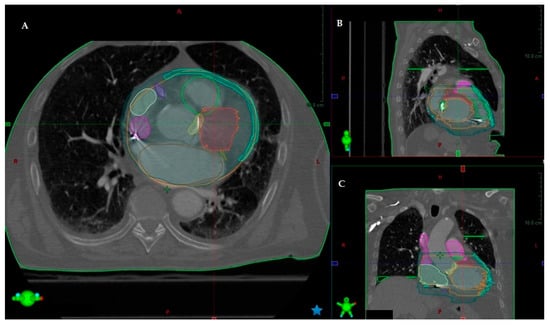

- Carbucicchio, C.; Jereczek-Fossa, B.A.; Andreini, D.; Catto, V.; Piperno, G.; Conte, E.; Cattani, F.; Rondi, E.; Vigorito, S.; Piccolo, C.; et al. STRA-MI-VT (STereotactic RadioAblation by Multimodal Imaging for Ventricular Tachycardia): Rationale and design of an Italian experimental prospective study. J. Interv. Card. Electrophysiol. 2021, 61, 583–593. [Google Scholar] [CrossRef]

- Conte, E.; Mushtaq, S.; Carbucicchio, C.; Piperno, G.; Catto, V.; Mancini, M.E.; Formenti, A.; Annoni, A.; Guglielmo, M.; Baggiano, A.; et al. State of the art paper: Cardiovascular CT for planning ventricular tachycardia ablation procedures. J. Cardiovasc. Comput. Tomogr. 2021, 15, 394–402. [Google Scholar] [CrossRef]